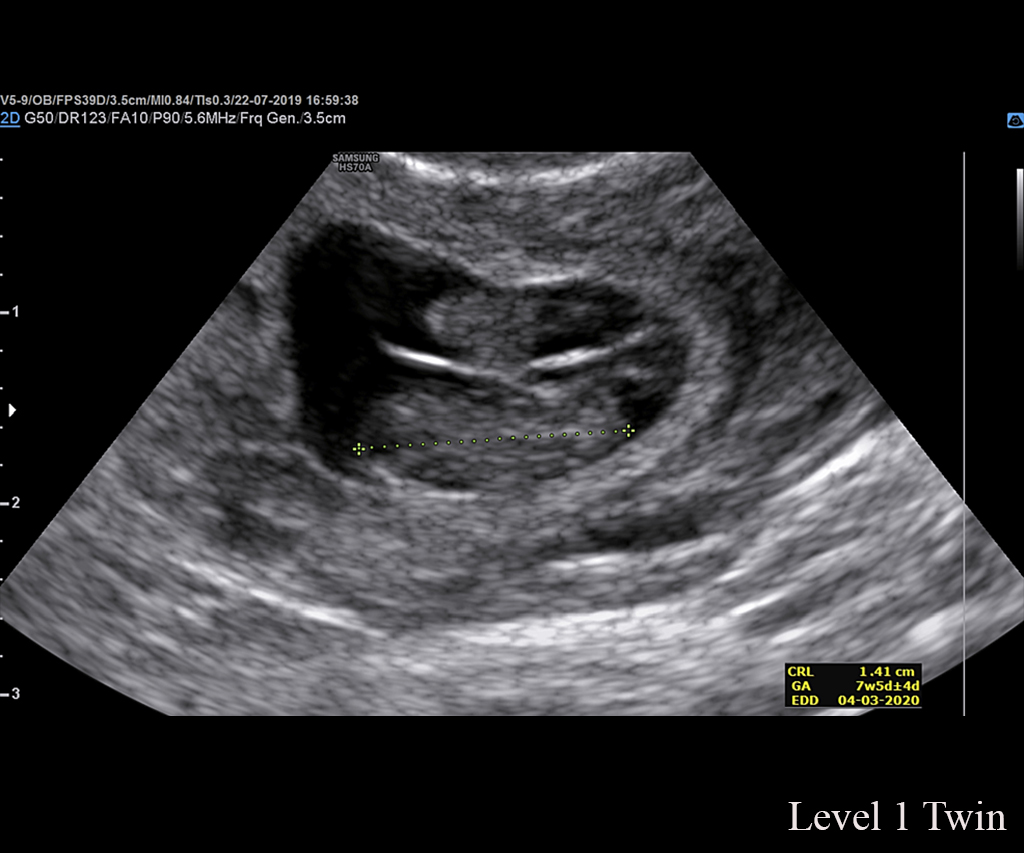

Ultrasound Level 1/NT Scan

Ultrasound Level 1/NT (Nuchal Translucency) Scan is a specialized prenatal screening test typically conducted between 11 to 14 weeks of pregnancy. It involves measuring the thickness of the nuchal fold, a small pocket of fluid at the back of the fetus’s neck, to assess the risk of chromosomal abnormalities such as Down syndrome and other genetic conditions. Additionally, the scan evaluates other fetal markers, including the nasal bone and blood flow in the ductus venosus and tricuspid valve. By combining these measurements with maternal age and other factors, the Level 1/NT scan provides an estimate of the fetus’s risk for certain chromosomal abnormalities, aiding expectant parents and healthcare providers in making informed decisions about further diagnostic testing or pregnancy management.